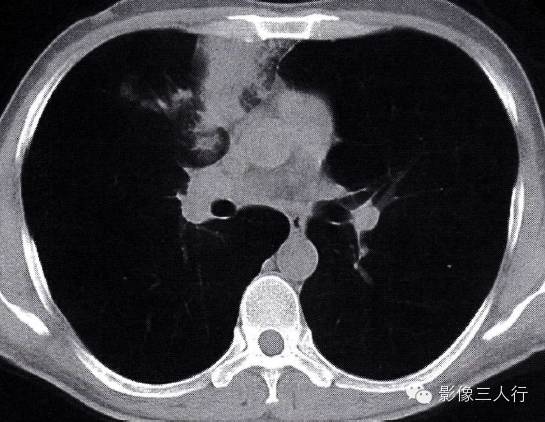

(4)周围模糊:相邻肺内有长条束状影,部分边缘模糊(图2-20,图2-21)。

图2-21  纵隔旁脓肿纵隔窗表现